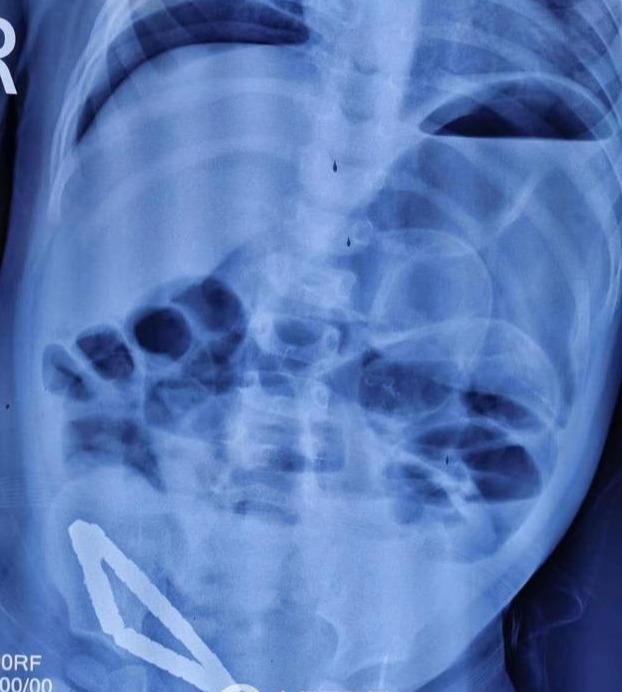

“孩子送到醫(yī)院后,精神萎靡,腹脹明顯,高燒39度,徐州市兒童醫(yī)院普外一科主任曹慧介紹說,由于孩子在當(dāng)?shù)蒯t(yī)院已經(jīng)檢查完善,我們看到檢查報告后,緊急擬定手術(shù)方案,立即安排手術(shù)。術(shù)中發(fā)現(xiàn)31個直徑幾毫米的小珠子串聯(lián)成一個三角形的形狀臥在小腸處,因為這種磁力珠吸力特別大,將患兒小腸緊緊'夾'住,造成患兒三處腸壞死和腸穿孔。深夜奮戰(zhàn)幾個小時最終我們將患兒體內(nèi)的31顆磁力珠全部取出,并截掉壞死小腸20cm左右,清理了腹腔的污染物,術(shù)后經(jīng)過一個星期治療,孩子可痊愈出院,但是小寶貝也遭了不少罪。”